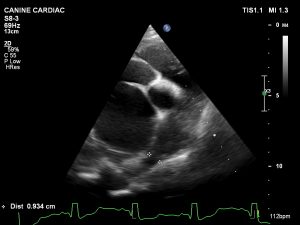

An echocardiogram showed a massive left side with both the Atrium and ventricle enlarged. The left atrium was so enlarged it made it difficult to get our normal views, but we found a clear PDA with a continuous flow in the pulmonary artery and a ductus of approximately 1.2cm. [See pics]